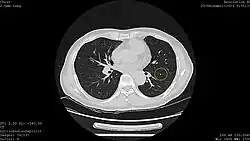

Results from large randomized studies have recently prompted a large number of professional organizations and governmental agencies in the U.S. to now recommend lung cancer screening in select populations. The 3 main types of lung cancer screening are low-dose, computerized tomographic (LDCT) screening, chest x-rays, and sputum cytology tests.[4] Currently multiple professional organizations, as well as the United States Preventive Services Task Force (USPSTF), the Centers for Medicare and Medicaid Services (CMS) and the European Commission's science advisors[5] concur and endorse low-dose, computerized tomographic screening for individuals at high-risk of lung cancer.

In the following years, the scientific community shifted its attention to computed tomography (CT). In 1996, results were published of a study of 1369 subjects screened in Japan that revealed that 73% of lung cancers that were missed by chest x-ray were detectable by CT scan.[19] Among the earliest United States-based clinical trials was the Early Lung Cancer Action Project (ELCAP), which published its results in 1999.[20] ELCAP screened 1000 volunteers with low-dose CT and chest x-ray. They were able to detect non-calcified nodules in 23% of patients by CT compared with 7% by chest x-ray. While this trial and a similar trial conducted by Mayo Clinic in 2005 demonstrated that CT was able to detect lung cancer at a higher rate than chest x-ray, both these trials used survival improvement, rather than mortality reduction, as an outcome, and thus were unable to prove that the use of CTs in lung cancer screening was actually impacting the number of people dying from lung cancer.[21][18]